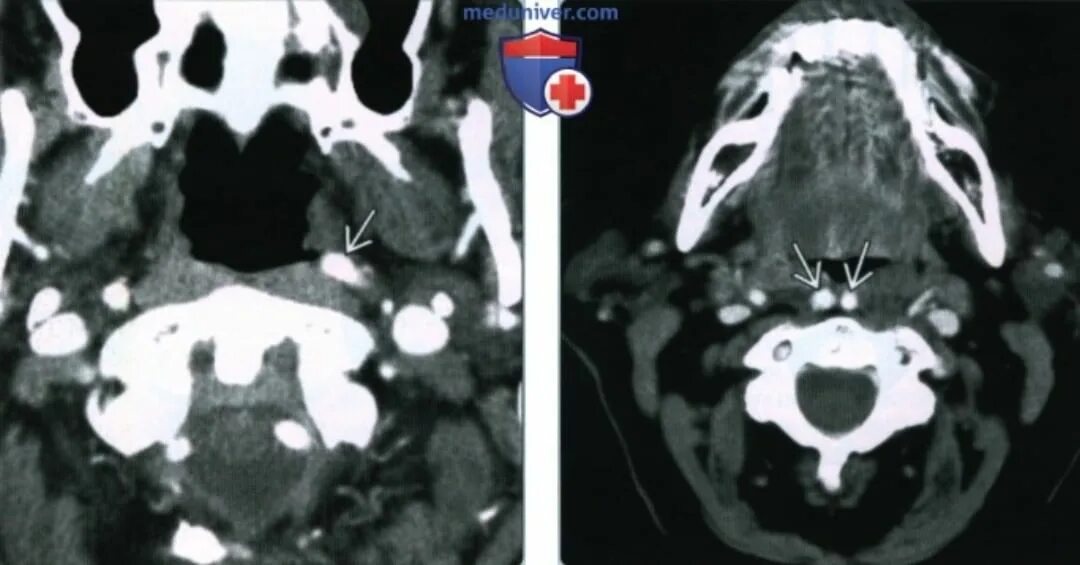

50 лет кт